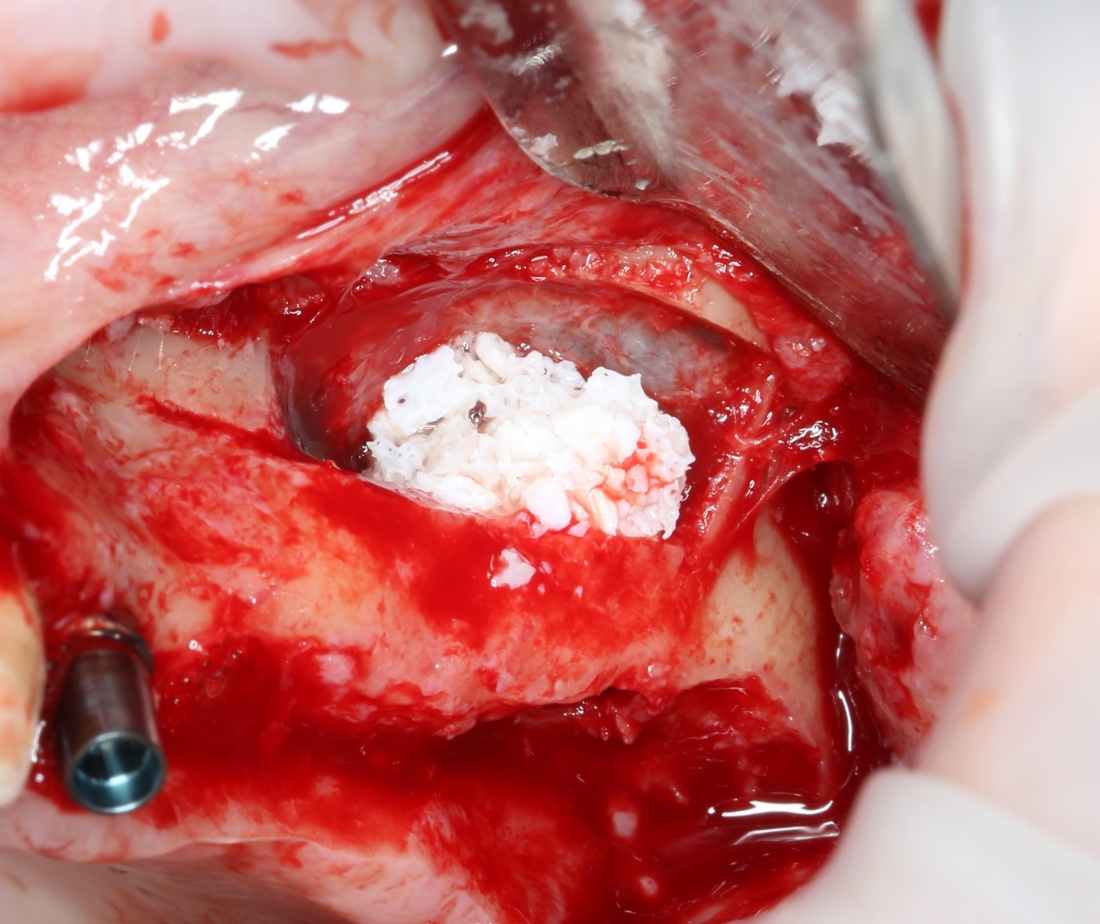

Кстати, обрати внимание на ширину альвеолярного гребня (левая картинка). Она чуть меньше 3 мм. Это объясняет, почему я засомневался в возможности установки имплантатов одновременно с остеопластикой. Понятно и без КЛКТ.

Наперво, мне нужно удалить разрушенный зуб и получить костный аутотрансплантат.

Для получения костного блока, мы открываем донорскую зону, наружную косую линию нижней челюсти.

Получение костного аутотрансплантата.

Здесь потребуется пародонтологический зонд с миллиметровой разметкой или какой-то другой измерительный прибор (операционная линейка). Ранее по КЛКТ я измерил костный дефект, теперь нужно нанести границы будущего костного блока на донорскую зону.

Для получения костного блока мы использовали ультразвуковую пьезохирургическую систему. Это самый удобный и безопасный инструмент для проведения подобных манипуляций. С помощью него мы сформировали и выделили костный блок. Он должен отделяться легким движением остеотома или элеватора. Как это сделать правильно — читай здесь>>

Подготовка костного ложа и фиксация аутотрансплантата

Возвращаемся к основной операционной области. Еще раз посмотрим на альвеолярный гребень, поофигеваем от его ширины и моих грандиозных планов:

Если ты читал мои предыдущие публикации, посвященные остеопластике, то наверняка знаешь, что костное ложе перед фиксацией графта (любого графта) требует некоторой подготовки. В основном она заключается в полном или частичном удалении кортикального слоя и, применительно к АТККФ — адаптации не только блока под ложе, но и ложа под пересаживаемый костный блок. Подробности здесь>>

Ежу понятно, что к необходимости этих манипуляций мы пришли не сразу. А тогда был 2013 год… и у меня были мысли, что подготовка костного ложа нужна не всегда и не всем. Здесь я понадеялся на размер костного дефекта и большую площадь контакта между костным аутотрансплантатом и принимающим ложем. Конечно, сейчас я сделал бы немного по-другому.

Я зафиксировал костный блок практически без адаптации на несколько винтов. Обрати внимание, что винты находятся в зоне, где не планируется установка имплантатов. Фиксация должна быть надежной, поскольку мне еще предстояла подготовка лунок для имплантатов. Трех винтов для этого вполне достаточно.